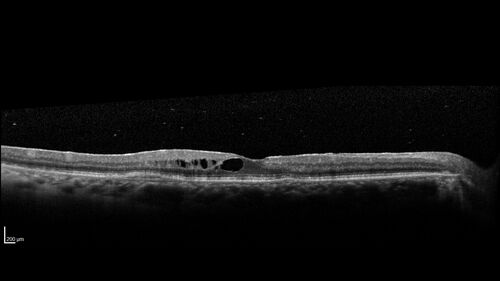

Birdshot Chorioretinitis - Chronic Untreated with Drusen Like Material in Macula

72 year old female with vision changes for years just now diagnosed with Birdshot.